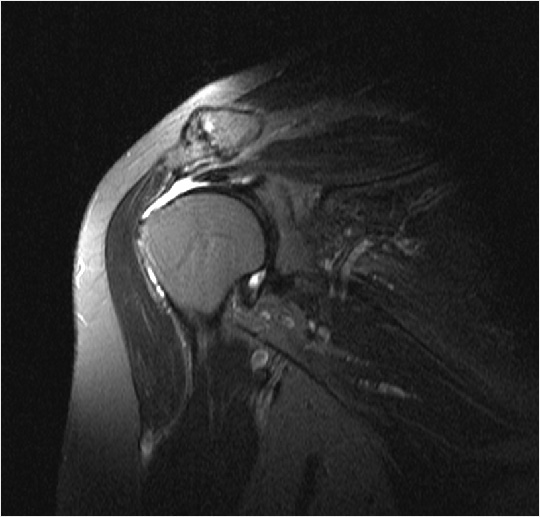

La diagnosi della lacerazione della cuffia dei rotatori è basata sull'esame clinico, delle radiografie e spesso anche della risonanza magnetica.

Questo esame permette di determinare l'estensione della lesione tendinea.